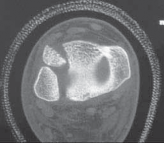

2. The distal tibial physis is for the most part transverse; however, there is an anterior medial undulation that consistently appears within the first 2 years of life that has been described by Kump (termed Kump’s bump). This central-medial location is where physiologic physeal closure begins (

FIG 1

).

FIG 1•

Kump’s bump. The

arrow

demonstrates the central-medial–located Kump’s bump, which is where physeal closure begins. We believe that damage to this structure may induce premature physeal closure.